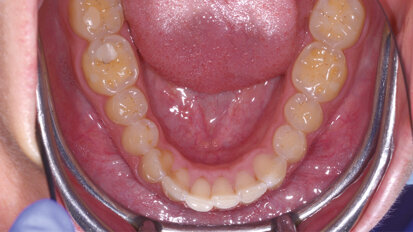

Protocollo sperimentale per la gestione dei tessuti duri durante il trattamento ortodontico

L’ortodonzia è la branca dell’odontoiatria che si occupa di prevenzione, diagnosi e trattamento delle alterazioni scheletriche a livello del massiccio ...